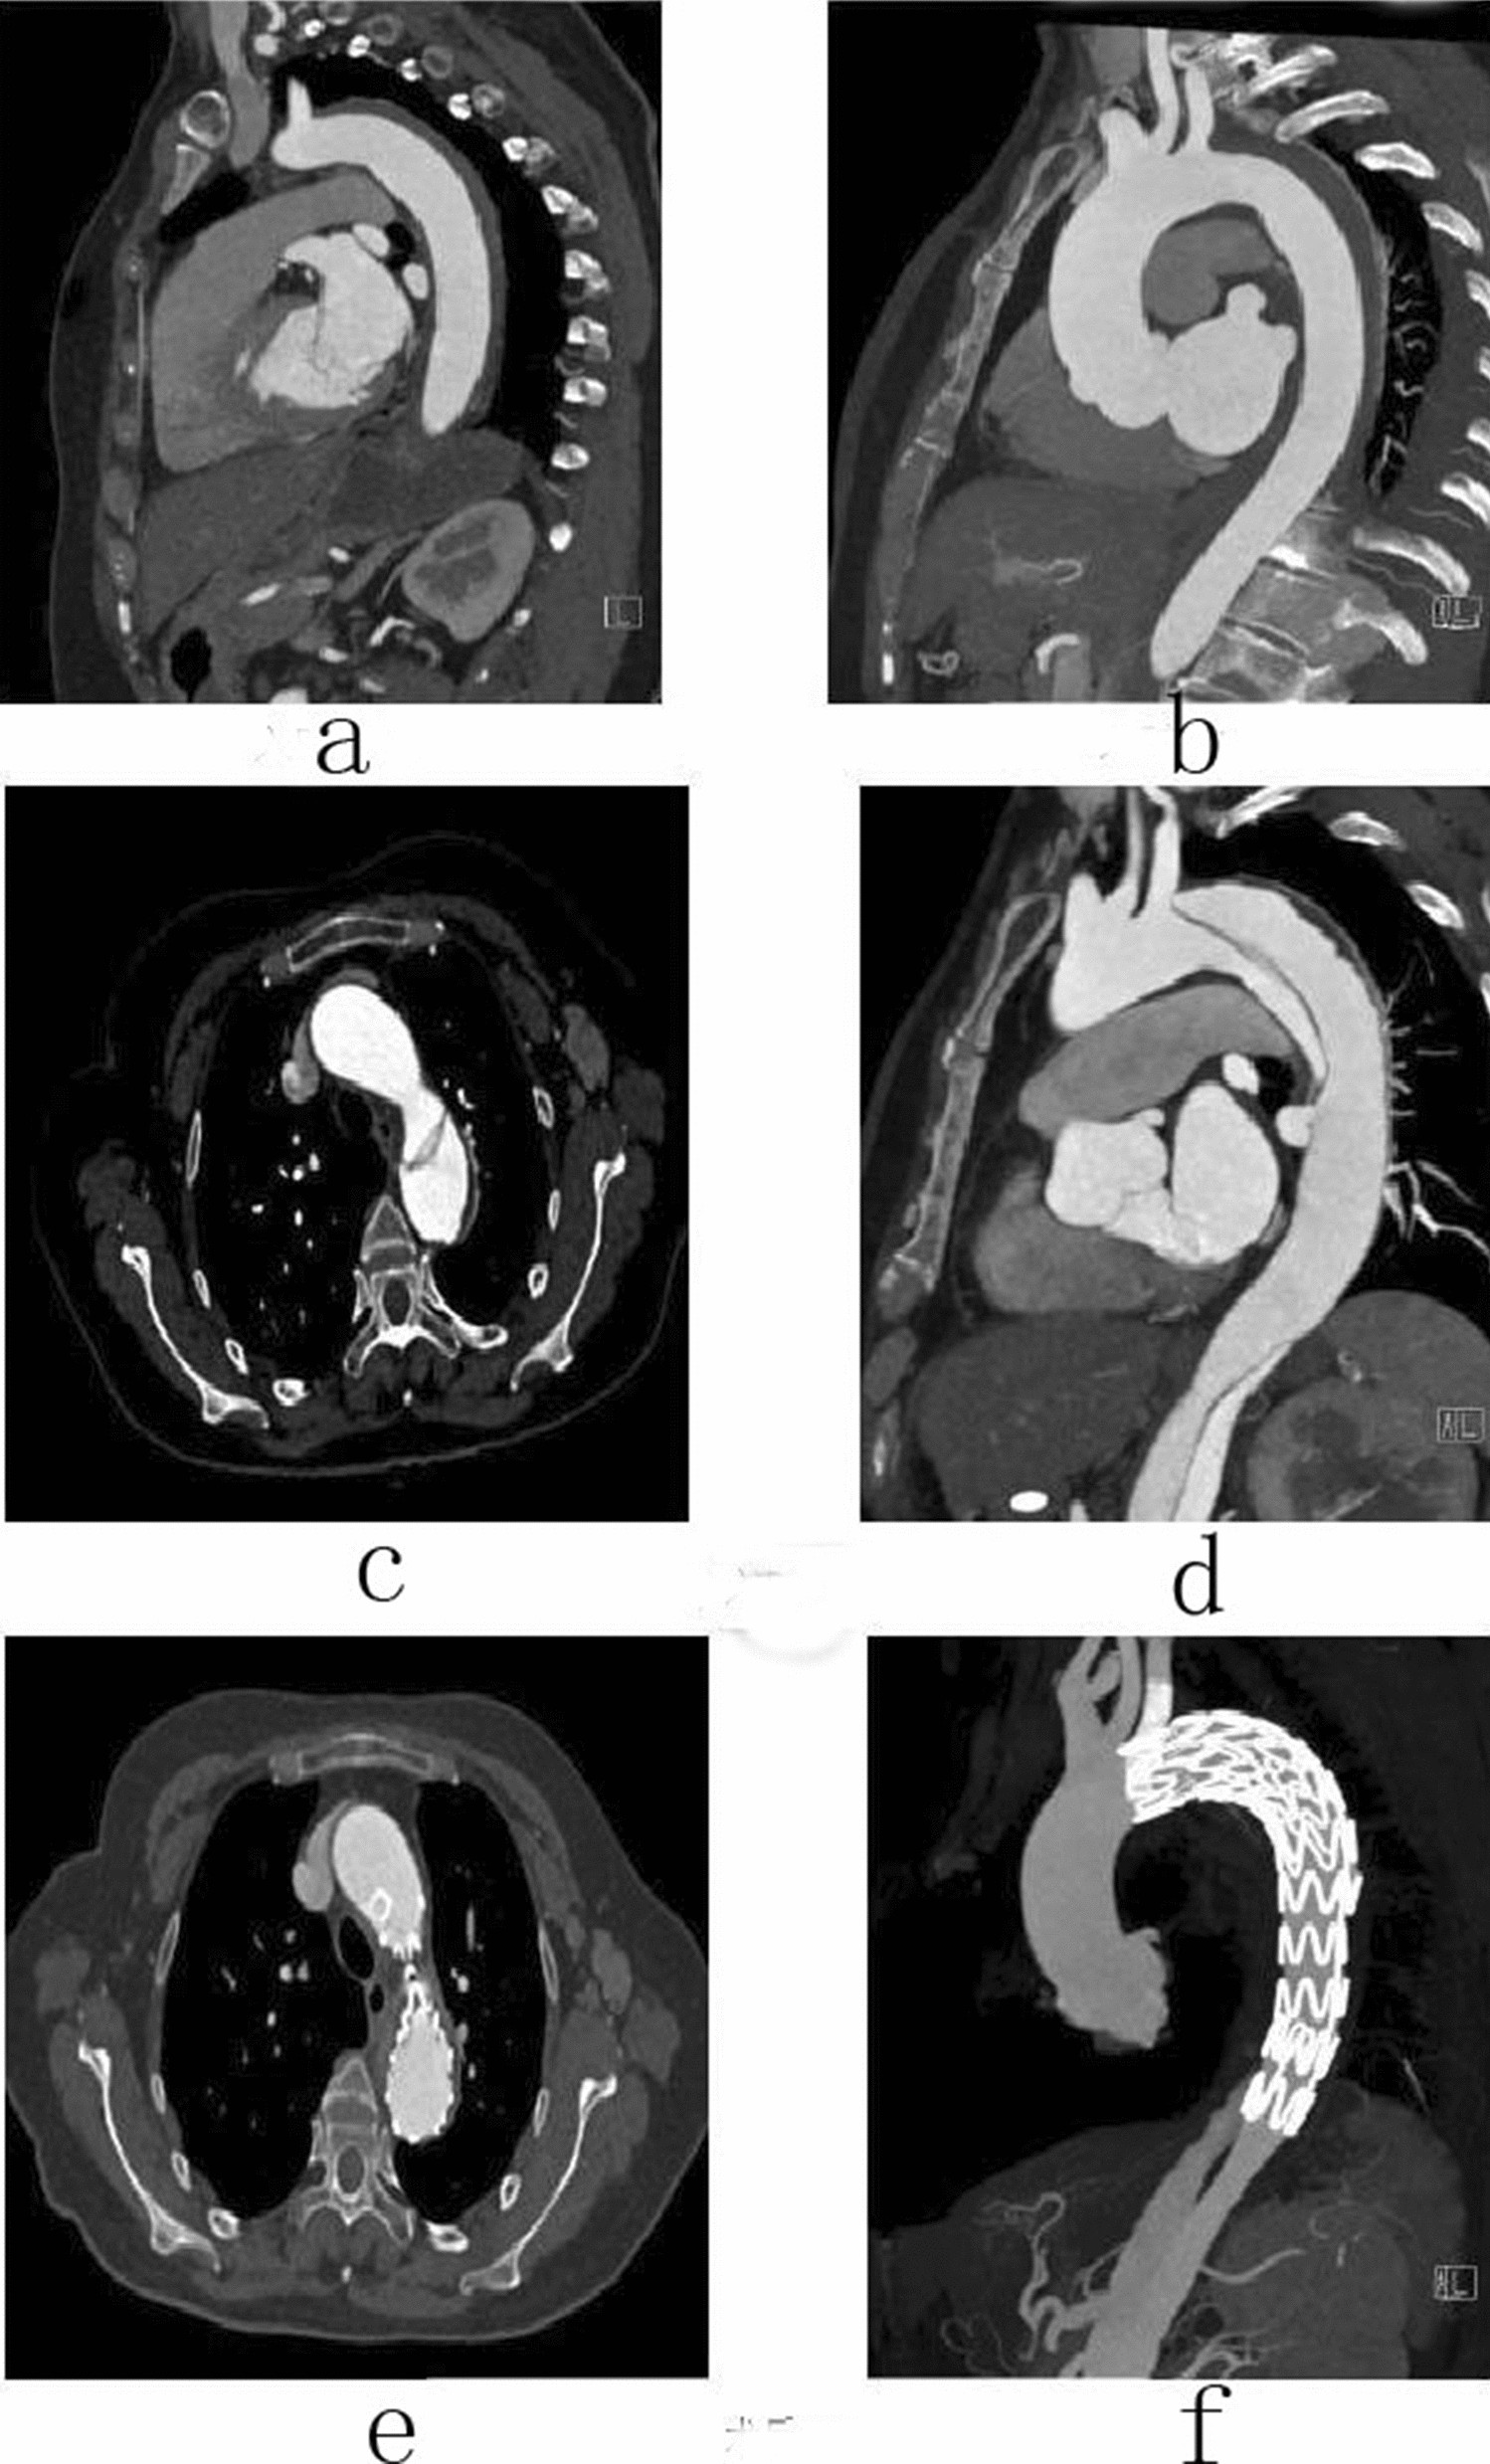

Figure 6

Female, 58 years old, admitted to hospital for “sudden pain in chest for 6 h”, Diagnosis: Stanford type B aortic dissection; Treatment: IMH TEVAR treatment. CTA of the patient in different periods: (a) Admission; (b) 5 days after admission; (c) 16 days after admission; (d) 16 days after admission; (e) 7 days after surgery; (f) 7 days after surgery.